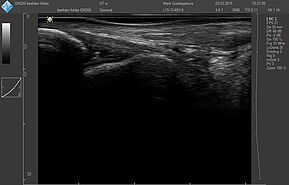

Области исследований:

- Костно-мышечная система

Система УЗИ поддерживает широкий диапазон трансдюсера нового поколения: монокристаллические, с элементами высокой плотности, широкополОсными и многочастотными от 1,0 МГц до 18,0 МГц:

Датчики имеют большую чувствительность и высокое разрешение, благодаря чему обеспечивают максимальное проникновение и улучшают соотношение сигнал /шум. В результате формируется максимально четкая детализированная картинка УЗИ изображения.